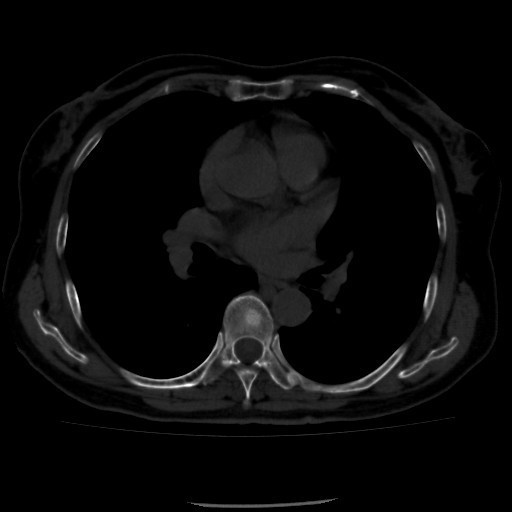

诊断:甲状腺恶性肿瘤(术后);手术后甲状腺功能减退。 治疗:入院时甲状腺球蛋白>455pmol/L,甲状腺素2.793uIU/ml,根据病情于2014-6-3予大剂量碘-131 100mCi清甲治疗;2014年6月全身碘扫示:全身多发异常摄碘组织,考虑甲状腺癌术后双侧甲状腺组织及锥状叶残留并全身多发骨转移。2014年9月胸部CT示:1、双肺多发转移瘤,并胸骨转移;胸1、8、10、腰1椎体内多发结节灶,考虑转移瘤可能性大。2、右肺中叶内侧段、双肺下叶散在慢性炎症。2014年12月全身碘扫:1.全身多处异常摄碘组织,考虑多发骨转移瘤。又于2014年12月复查甲状腺球蛋白抗体90.400U/mL,促甲状腺素6.914uIU/ml。遂于2014-12-22口服250mCi大剂量放射性碘-131。治疗后全身碘扫复查结果提示:2.左肺下叶摄碘组织,不排除转移瘤,建议进一步检查。与2014.6.6检查相比,颈部甲状腺部位放射性浓集灶消失,余病灶放射性浓集程度较前稍降低。

患者又于2015年10月胸部CT复查,结果提示:1、甲癌术后改变;双肺多发转移瘤,大部分病灶较前缩小,左肺下叶病灶较前增多,部分较前增大;胸骨转移;胸1、8、10、腰1椎体内多发结节灶,基本同前,考虑转移瘤可能性大。2、右肺中叶内侧段、左肺上叶舌段及双肺下叶散在慢性炎症。